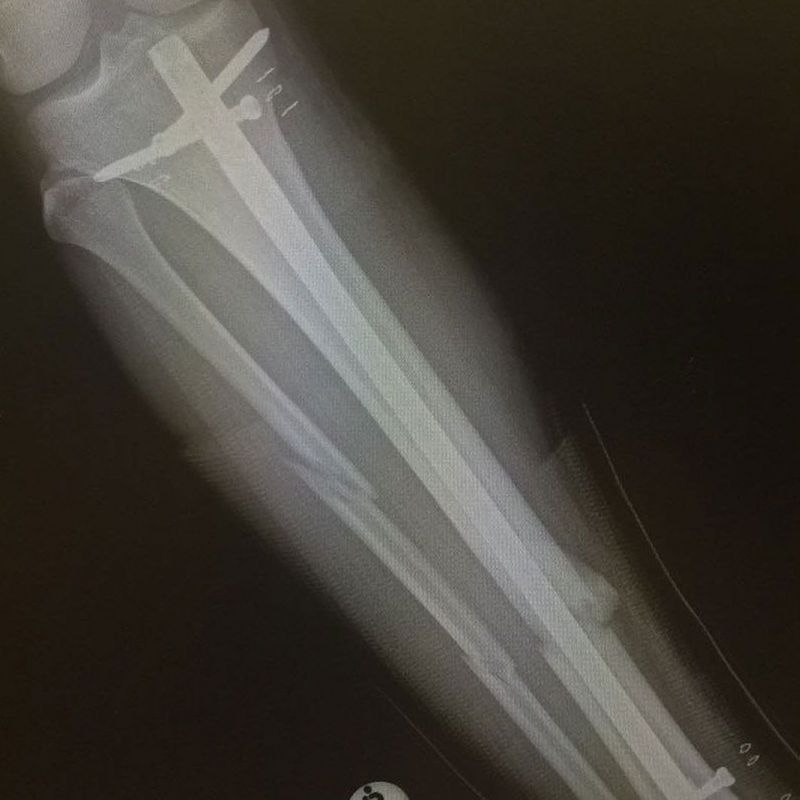

von Lars NiggemeyerLetztes Jahr konnte Alessio Stillrich seine bisher beste Saison auf der PWA Wave-Worldtour feiern. Das erste mal in seiner Karriere brach der 23-jährige Deutsch-Kanario in die Top-10 der Welt ein. Schon bei seinem Worldcup-Debüt an seinem Homespot Pozo Izquierdo auf Gran Canaria in 2009 hatte er für Aufsehen gesorgt. Niemand hatte bis dato derart verdrehte Tweaked-Pushloops in solcher Höhe gesehen, wie Stillrich sie zeigte. Seitdem hat er sich konsequent weiterentwickelt und sich - seitdem er Voll-Profi ist - jedes Jahr in der Weltrangliste weiter nach oben gearbeitet. Leider ist Stillrichs nächste Saison nun komplett in die Binsen gegangen. Im südafrikanischen Kapstadt zog er sich beim Training einen komplizierten und überaus schmerzhaften Beinbruch zu. Sechs Monate darf er nicht aufs Wasser. Im WINDSURFERS Interview berichtet Alessio über seinen Unfall.

Nach Meinung meines Arztes verläuft die Genesung nach Plan. Leider brauchen Schien- und Wadenbein vier Monate um wieder zusammenzuwachsen. Reha mache ich natürlich täglich und wir merken meine Fortschritte von Tag zu Tag. Ich bin in der Wohnung nach dem Okay vom Arzt schon ohne Krücken unterwegs. Schwimmen darf ich auch schon seit ein paar Wochen. Es geht also aufwärts, obwohl es schwer ist die Geduld zu bewahren.